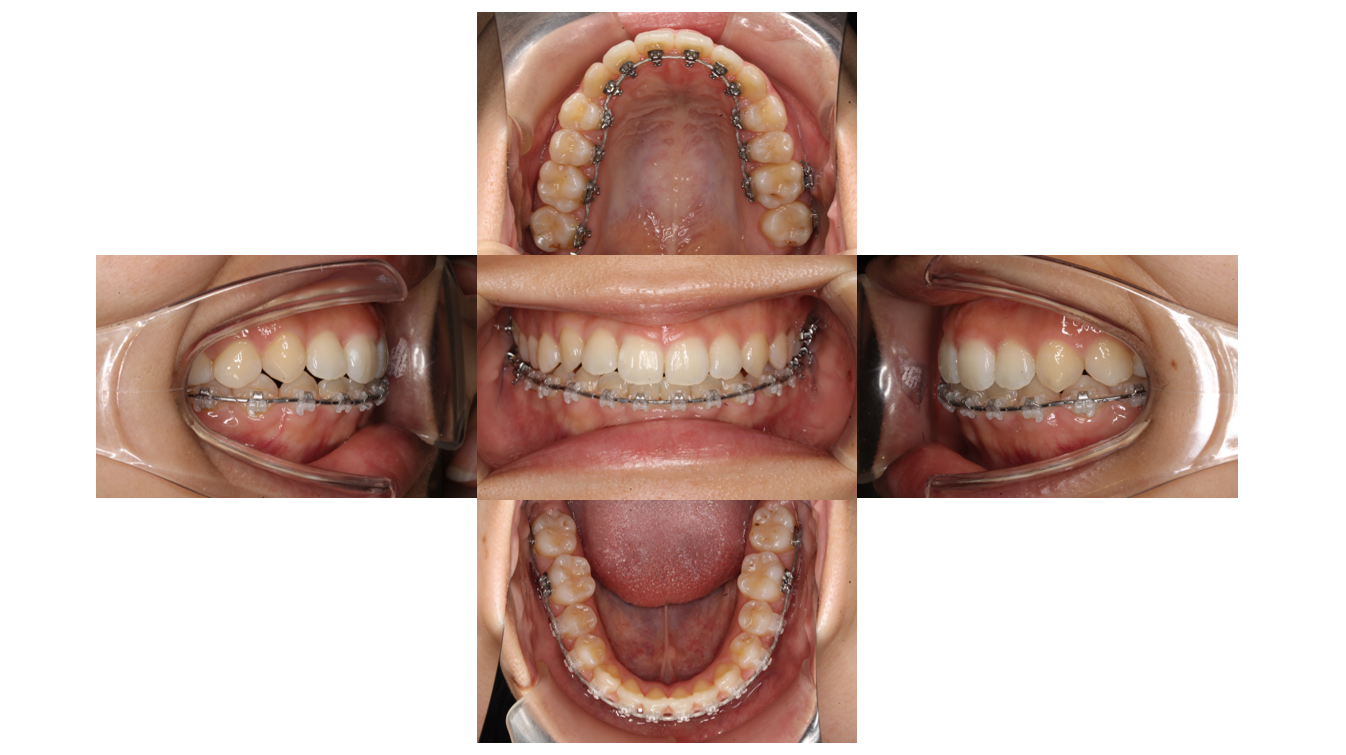

1年経過

全体的にゴムをかけて歯と歯の間に隙間が空いてこないようにします